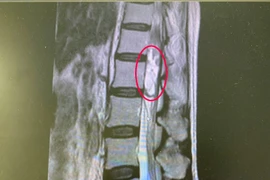

Có hiện tượng đau cột sống thắt lưng, đau lan xuống 2 chân kèm tê bì, người phụ nữ không ngờ được phát hiện u tủy sống. U tủy sống có thể lành tính hoặc ác tính, cần phát hiện sớm.

U tuỷ sống là một trong những bệnh lý nguy hiểm, dễ liệt và tử vong nhưng các triệu chứng lâm sàng ban đầu rất mơ hồ, dễ nhầm lẫn với các bệnh lý cơ xương khớp thông thường.